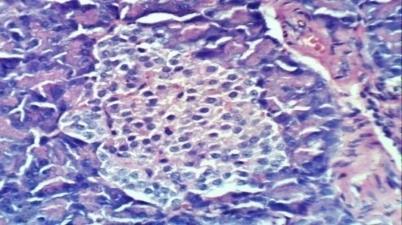

![]() |

Fig. 2(b): Liver of diabetic rats showed hydropic degeneration of hepatocytes, sinusoidal leukocytosis and congestion of hepatoportal blood vessel (H & E X 400) |

The biochemical parameters were documented with histopathological finding which reveal hydropic degeneration of hepatocytes, sinusoidal leukocytosis and congestion of hepatoportal blood vessel in diabetic rats (photo 2b). While the kidney of diabetic rat showed atrophy of glomerular tuft and thickening of the parietal layer of Bowman’s capsule (photos 3b and 3c). Also, Pancreas of diabetic rat exhibited vacuolation of epithelial lining pancreatic acini (photo 4d). Treatment of diabetic rats with ethanol extracts of F. japonica demonstrated normal histological structure in kidney and pancreas architectures (photo 3c, 4c and 4c), while portal oedema was reported in liver (photo 2 c).